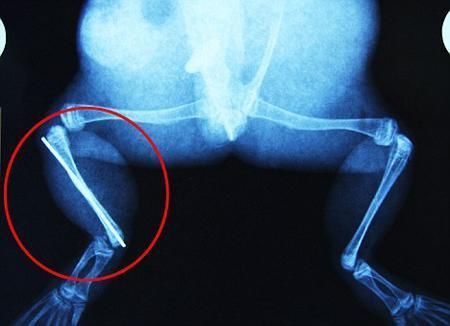

布魯萊的主人,居住在南非約翰內(nèi)斯堡附近的62歲的安妮·米恩斯說:“我對(duì)這只青蛙如此關(guān)心,人們一定認(rèn)為我瘋了,但是我無法眼睜睜看著它那么痛苦。青蛙因其靈活的腿腳而著稱,一想到布魯萊的腿里要留下一個(gè)薄金屬片,我就感到心痛。然而我知道,如果不進(jìn)行手術(shù),布魯萊以后就沒辦法動(dòng)彈了。因此我匆匆趕到獸醫(yī)那里,央求他給這只可憐的青蛙動(dòng)手術(shù)。這位獸醫(yī)整天救助小貓小狗,他很難理解為什么我這么擔(dān)心一只青蛙,但是最終他還是答應(yīng)了給布魯萊做手術(shù)。手術(shù)后是幾個(gè)小時(shí)的焦急等待,我們希望它能快快蘇醒過來。不過現(xiàn)在它的傷口已經(jīng)愈合,又能在花園里跳來跳去了。X光照射顯示,它會(huì)恢復(fù)的跟以前一樣。”

野生生物專家安妮經(jīng)常為學(xué)校寫教材,她認(rèn)為這是人類第一次通過手術(shù)給一只青蛙接斷腿。在手術(shù)開始階段,獸醫(yī)把少量給狗用的麻醉藥注入到這只青蛙體內(nèi),讓它失去知覺。然后他在布魯萊的斷腿上切開一個(gè)小口,把一根小鋼針植入腿里。最后獸醫(yī)給它縫了9針,把切口縫合在一起。僅僅幾周后,布魯萊就能在安妮家附近活動(dòng)了。這只青蛙大約已有25歲,主要以嚙齒動(dòng)物、蛇和其他青蛙為食。布魯萊所屬的牛蛙種群正在不斷減小,目前只能在非洲南部的濕地里才能看到這種青蛙。